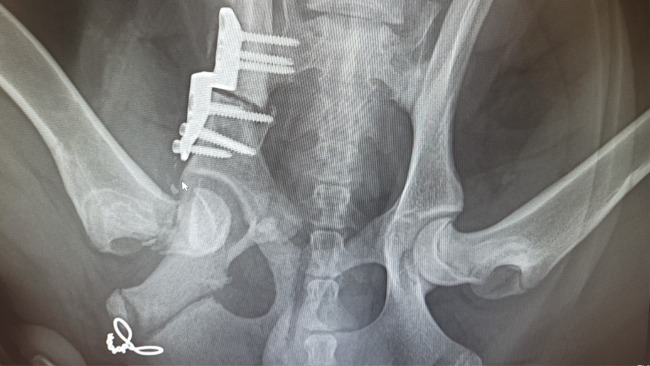

Zachowanie Kokosa nas niepokoiło, było czuć pod dłonią w miejscu opweiwwnym że coś się porusza. Szybkie RTG - złamanie główki kości udowej.. Z niczyjej winy - ryzyko, powikłanie po zabiegu 😭 (miejsce gdzie widoczna jest myszka komputerowa).

Kokos został w szpitalu i miał kolejny zabieg aby złączyć te kości i ostatecznie ma kolejną ranę oraz gips.. Porusza się na 3 łapach, gips uciska mu cewkę moczową co utrudnia oddawanie moczu..